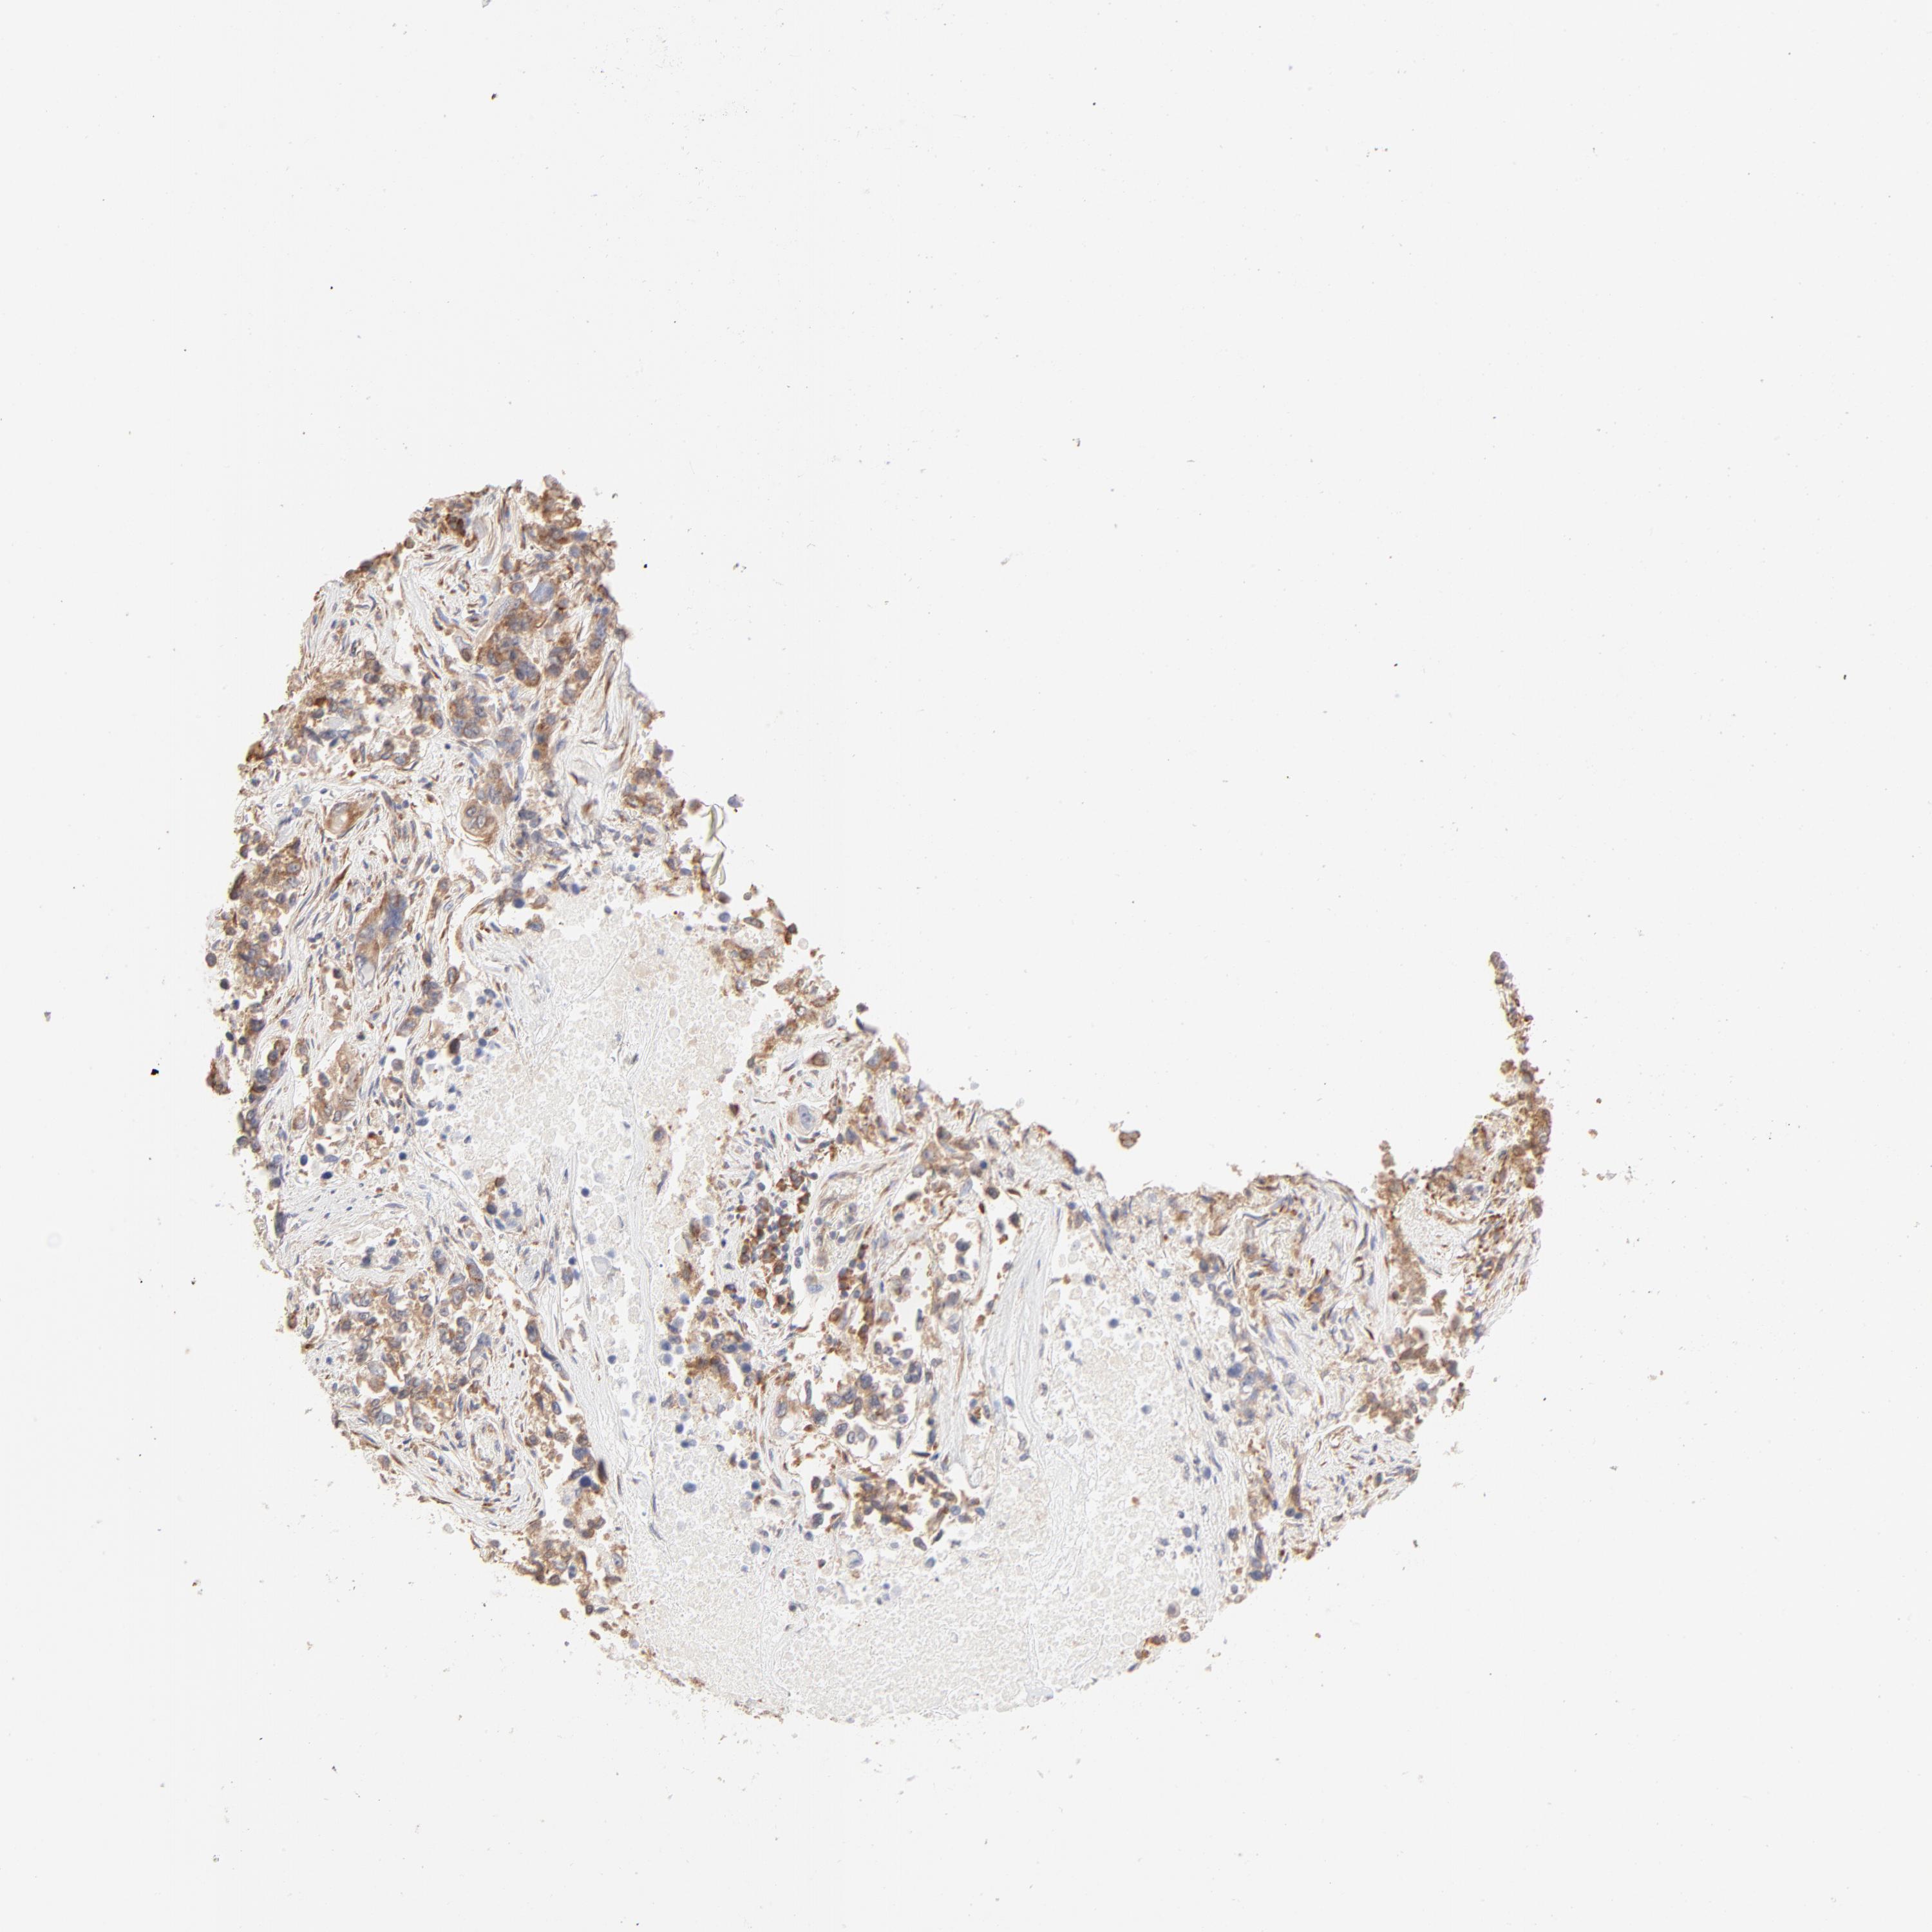

CANCER LUNG CANCER Show tissue menu

Lung cancer

Human cancer

LUNG ADENOCARCINOMA (TCGA) - Interactive survival scatter ploti

The Survival Scatter plot shows the clinical status (i.e. dead or alive) for all individuals in the patient cohort, based on the same data that underlies the corresponding Kaplan-Meier plots. Patients that are alive at last time for follow-up are shown in blue and patients who have died during the study are shown in red.

The x-axis shows the expression levels (FPKM) of the investigated gene in the tumor tissue at the time of diagnosis. The y-axis shows the follow-up time after diagnosis (years). Both axes are complimented with kernel density curves demonstrating the data density over the axes. The top density plot shows the expression levels (FPKM) distribution among dead (red) and alive patients (blue). The right density plot shows the data density of the survived years of dead patients with high and low expression levels respectively, stratified using the cutoff indicated by the vertical dashed line through the Survival Scatter plot. This cutoff is automatically defined based on the FPKM cutoff that minimizes the p-score. The cutoff can be changed by dragging the vertical line or by entering a cutoff value in the square labeled "Current cut-off".

Under the Survival Scatter plot the p-score landscape (black curve; left axis) is shown together with dead median separation (red curve; right axis). Dead median separation is the difference in median mRNA expression between patients who have died with high and low expression, respectively. It is calculated as follows: median FPKM expression of dead patients with high expression - median FPKM expression of dead patients with low expression. This is intended to aid the user in visually exploring custom cutoffs and the associated p-scores and dead median separation.

Individual patient data is displayed and can be filtered by clicking on one or more of the category buttons on the top of the page. Categories describing expression level and patient information include: high, low, alive, dead, female, male and tumor stages. The scale of the x-axis can be toggled between linear and log-scale by clicking on the "x log" button. Mouse-over function shows TCGA ID, patient information and mRNA expression (FPKM) for each patient.

& Survival analysisi

Kaplan-Meier plots summarize results from analysis of correlation between mRNA expression level and patient survival. Patients were divided based on level of expression into one of the two groups "low" (under cut off) or "high" (over cut off). X-axis shows time for survival (years) and y-axis shows the probability of survival, where 1.0 corresponds to 100 percent.

RPS21 is not prognostic in Lung Adenocarcinoma (TCGA)